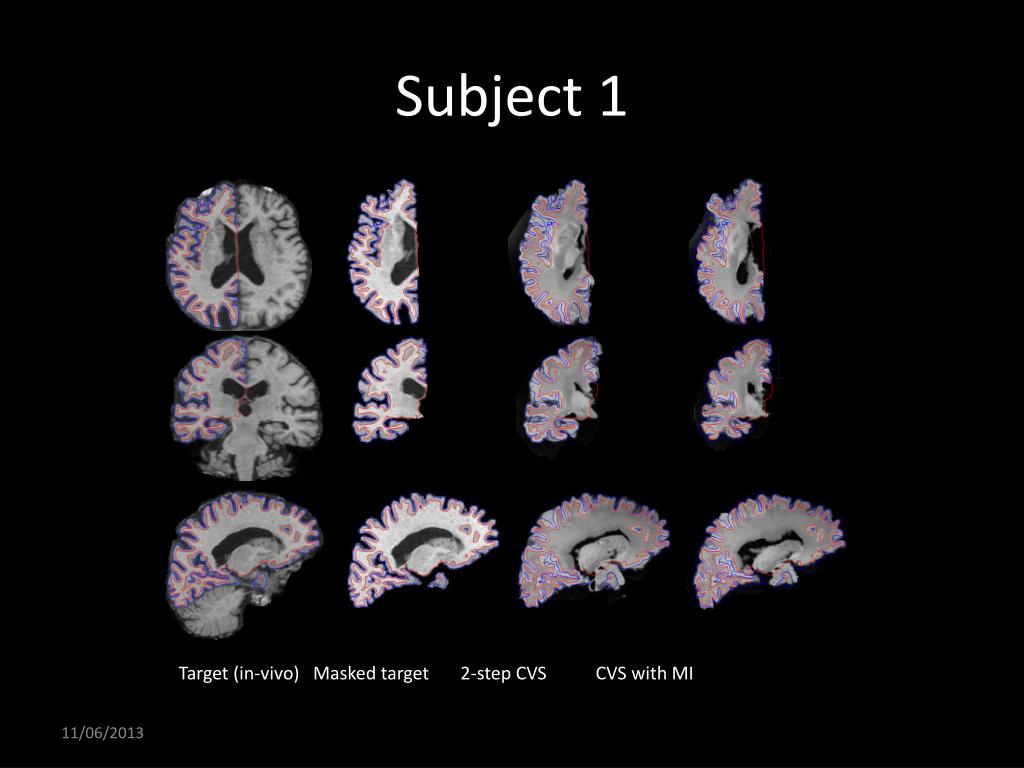

23. Ongoing development • Improve CVS capability to register ex-vivo to in-vivo acquisitions • Implemented MI-based volumetric registration (for CVS step 3) to accommodate intensity profile differences • Qualitative preliminary results on 4 subjects • L. Zöllei, Allison Stevens, Bruce Fischl: Non-linear Registration of Intra-subject Ex-vivo and In-vivo Brain Acquisitions, Human Brain Mapping, June 2010 • L. Zöllei, B. Fischl, Automatic segmentation of ex-vivo MRI images using CVS in FreeSurfer, HBM 2011

24. Target (in-vivo) Masked target 2-step CVS CVS with MI Subject 1